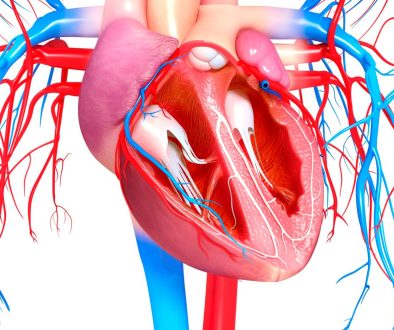

عتبر أمراض القلب من بين أكثر المشكلات الصحية شيوعاً وخطورة على مستوى العالم. لذا من الضروري تعزيز الوعي والمعرفة حول كيفية تشخيص هذه الأمراض وطرق علاجها المختلفة. تهدف هذه المقالة إلى تقديم نصائح وتعليمات تثقيفية تسهم في تحسين جودة حياة الأفراد الذين يعانون من أمراض القلب.

2. **العلاجات الجراحية**:

– حالات تستدعي التدخل الجراحي مثل انسداد الشرايين أو عيوب الصمامات القلبية.

– إجراءات مثل تركيب الدعامات القلبية وتوسيع الشرايين يتم استخدامها لتقليل الانسداد وتحسين تدفق الدم.